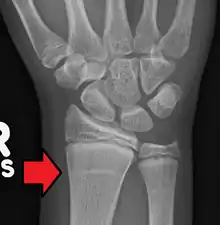

Growth arrest lines in a child with an underlying bone disease | |

Growth arrest lines, also known as Harris lines, are lines of increased bone density that represent the position of the growth plate at the time of insult to the organism and formed on long bones due to growth arrest. They are only visible by radiograph or in cross-section. The age at which the lines were formed can be estimated from a radiograph. Harris lines are often discussed as a result of juvenile malnutrition, disease or trauma. Other studies suggest a reconsideration of Harris lines as more of a result of normal growth and growth spurts, rather than a pure outcome of nutritional or pathologic stress.[1] The lines are named after Henry Albert Harris, 1886-1968, professor of anatomy at the University of Cambridge.[2]